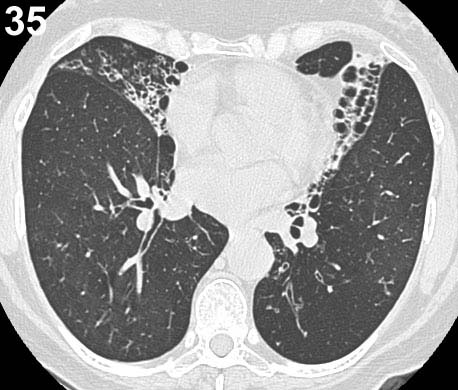

ESQUEMA 34 Comentario placa 34 En la base izquierda y área vecina al borde derecho del corazón hay sombras irregulares dentro de las cuales se distingue con dificultad algunas imágenes areolares mal definidas. Si bien esto permite plantear la sospecha de bronquiectasias su confirmación necesita de una TAC, que es mucho mas sensible para detectar estas alteraciones, como puede apreciarse en la placa que sigue.